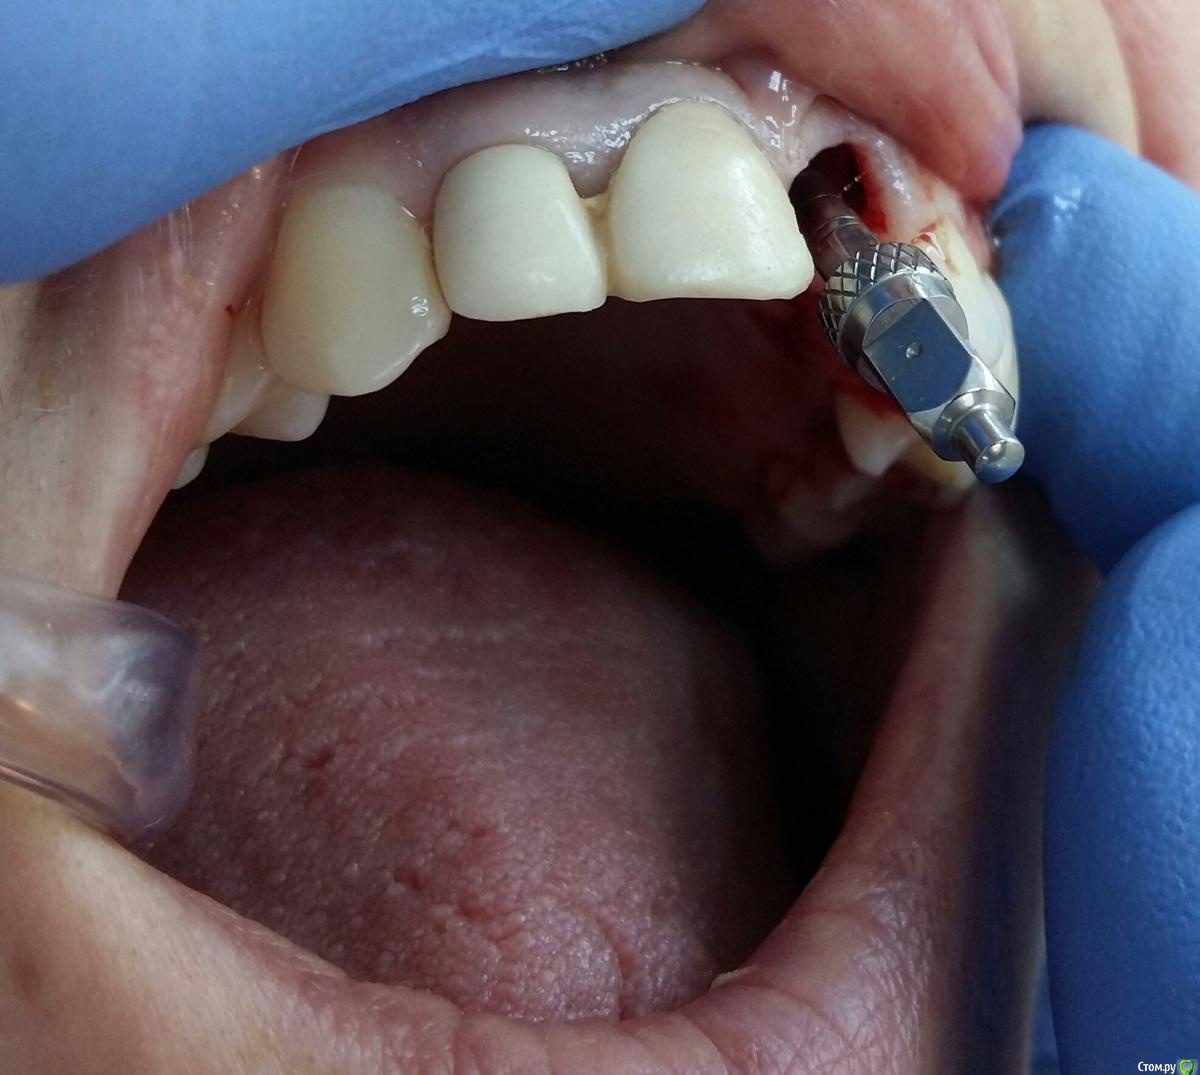

Kostoprav Опубликовано 8 ноября, 2017 Поделиться Опубликовано 8 ноября, 2017 заранее извиняюсь за качество фотографийдумал сделать все в один этап но торка ожидаемого не получил, поэтому пришлось накрыть винт випом.(материал osteobiol putyy) мне он очень понравиля ,удобный в работе. 17 Ссылка на комментарий

Kostoprav Опубликовано 8 ноября, 2017 Автор Поделиться Опубликовано 8 ноября, 2017 Торк был не достаточный для временной реставрации. Около 20. Я не рискнул.Срезы если найду выложу, хотя там ситуация стандартная ничего из ряда вон выходящего Ссылка на комментарий